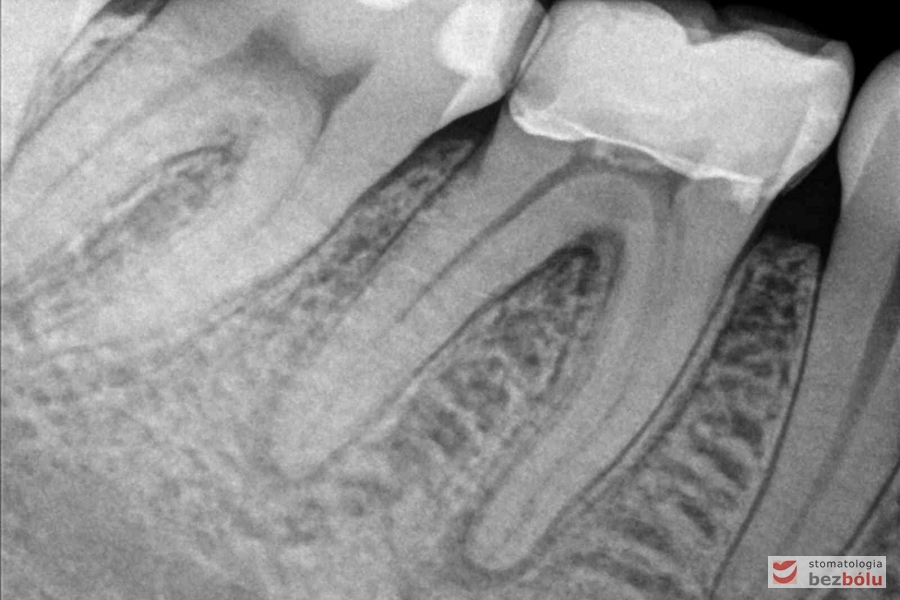

Radiowizjografia - widoczna zmiana okołowierzchołkowa szóstki po stronie prawej w żuchwie

Radiowizjografia – widoczna zmiana okołowierzchołkowa szóstki po stronie prawej w żuchwie